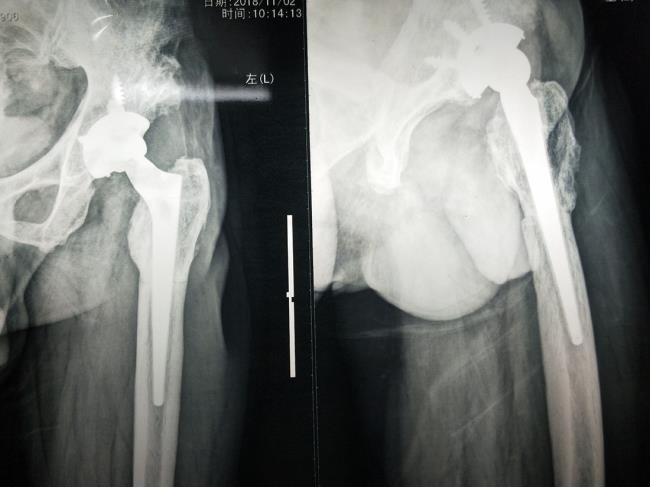

开展数字化技术,3D打印技术

开展数字化技术,3D打印技术在骨科诊疗中的应用,提高骨科诊疗水平,获得广西科技厅重大专项建设项目。

开展人工髋、膝关节置换手术